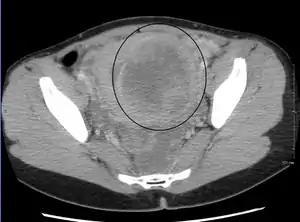

A very large (9 cm) fibroid of the uterus which is causing pelvic congestion syndrome as seen on CT

A very large (9 cm) fibroid of the uterus which is causing pelvic congestion syndrome as seen on ultrasound